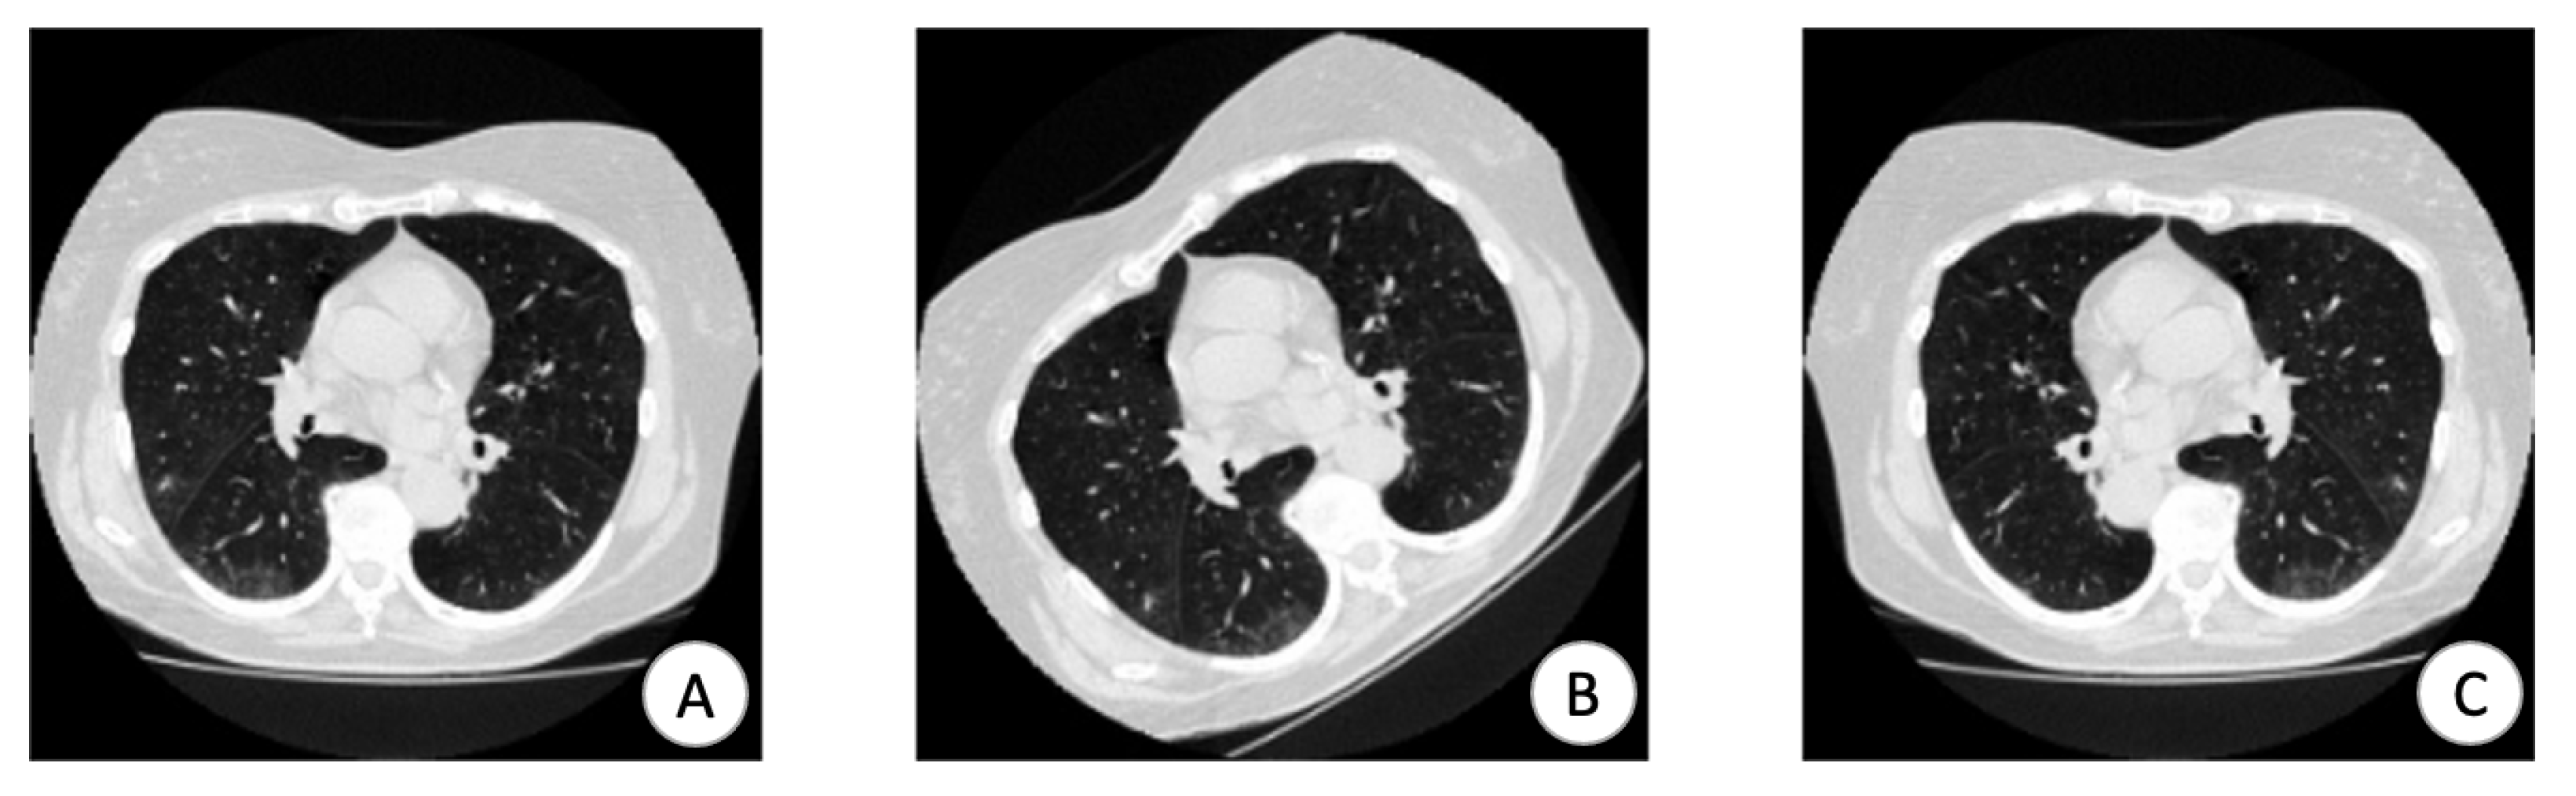

2.1. Data Preprocessing